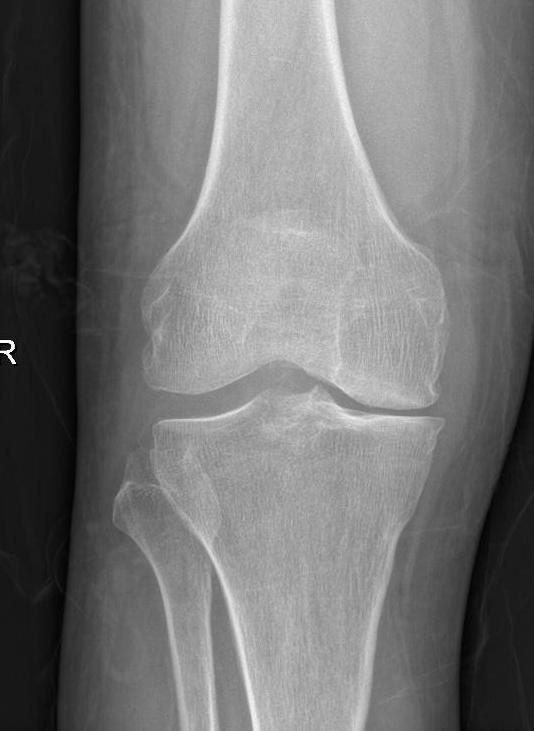

图5 胫骨高位截骨手术前x片

图5 胫骨高位截骨手术后x片。

图5 :术前x片显示左膝关节内侧狭窄,膝关节(胫骨)内翻;术后下肢力线向膝关节外侧转移,膝关节内翻得到纠正,改善了膝关节内侧受力,缓解内侧疼痛